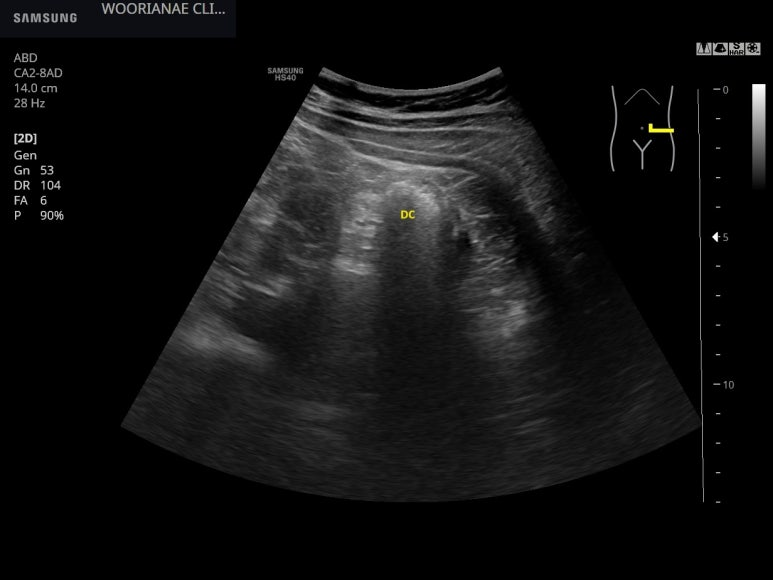

하행결장 (DC)

하행결장의 끝에서 전방으로 염증성 종괴같이.. 고음영의 난원형 변화가 인지되며

리니어 프로브로 아래와 같이 저음영 경계를 가지는 고음영 종괴로 관찰된다.